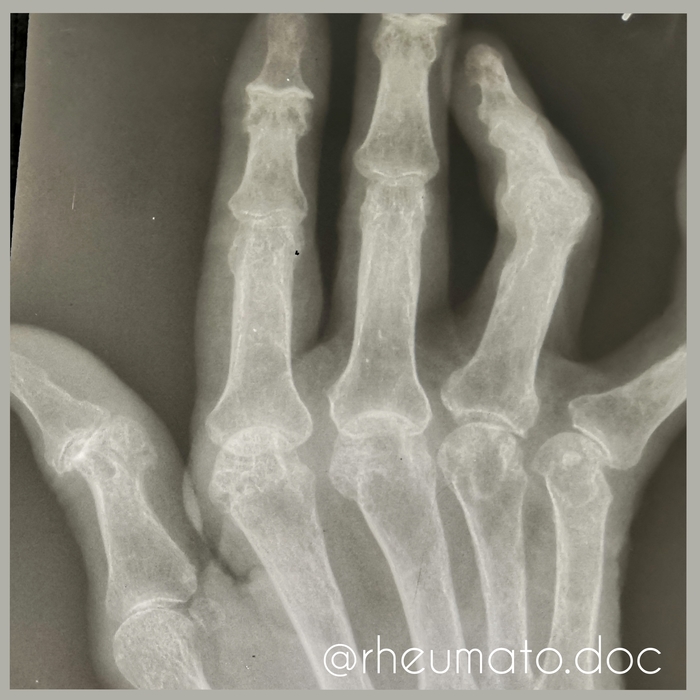

Клинический пример.

Жила-была девушка, любительница фитнеса, правильного питания и маленьких собачек. Во время ежедневной пробежки попала под дождь, сверкает молния, собачка убегает - она за ней. Пока догнала, простудилась. Температура 37,8С, насморк и все еще дрожащая собачка. За 7 дней все прошло, собачка успокоилась. Но остался какой-то дискомфорт в руках. Потом дискомфорт перешел в боль, суставы припухли, стало сложно сгибать.

Что мы с вами можем предположить из того, что уже знаем? Вирусная инфекция запустила аутоиммунный процесс (предрасположенность к которому у неё была) , стало много воспалительных клеток и они поразили синовиальную оболочку. В этом случае воспалительный процесс проявился болью, отеком и нарушением функции. Что если никак не вмешиваться в этот процесс? Воспаление будет продолжаться, хрящ начнет разрушаться, затем в процесс подключится костная ткань. Как только хряща не останется деформированные кости срастутся между собой (это называется анкилоз), кисть при этом уже мало что способна выполнять. Как только случится анкилоз, боль, как правило, уходит.